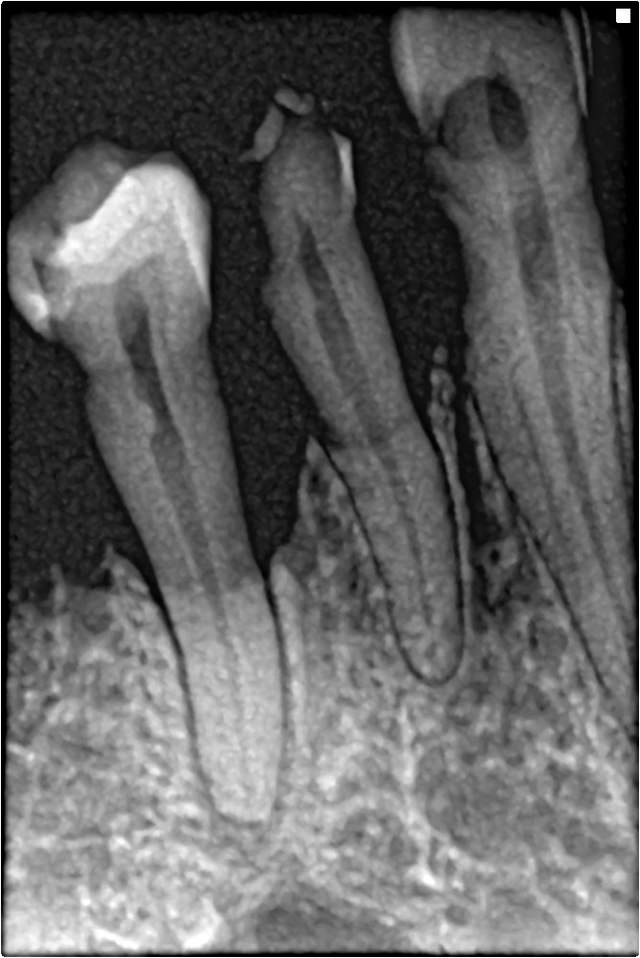

잇몸이 심각하게 내려앉으면 뿌리가 드러나게 되고, 치아가 흔들리고, 발치까지 해야 하는 상황이 발생합니다ㅠㅠ..

2. 치석이 많이 쌓이고 잇몸 내려앉음 증상이 진행되고 있는 상태 : 뿌리 깊이까지 쌓여있는 치석들을 제거하기 위해 잇몸 치료가 필요합니다.(치은연하 치석제거술) 잇몸치료는 마취도 필요하고 시간이 오래 걸리는 치료법이라 보통 4-6번에 나눠서 치료하게 됩니다.

3. 치석과 염증이 잇몸 깊숙이 쌓여 잇몸 내려앉음 증상이 많이 진행된 상태 : 눈으로 보이지 않는 잇몸 깊숙한 곳의 염증과 치석을 제거하기 위해 잇몸을 절개하는 잇몸 수술이 필요합니다. (치은 박리 소파술)

▲ 치아의 3분의 2를 덮고 있는 건강한 잇몸

▲(좌) 건강한 잇몸/ (우) 이미 많이 내려앉은 잇몸

▲ 이렇게 잇몸이 내려앉게 되면 미관상으로도 좋지 않은 것 같아요ㅠㅠ..